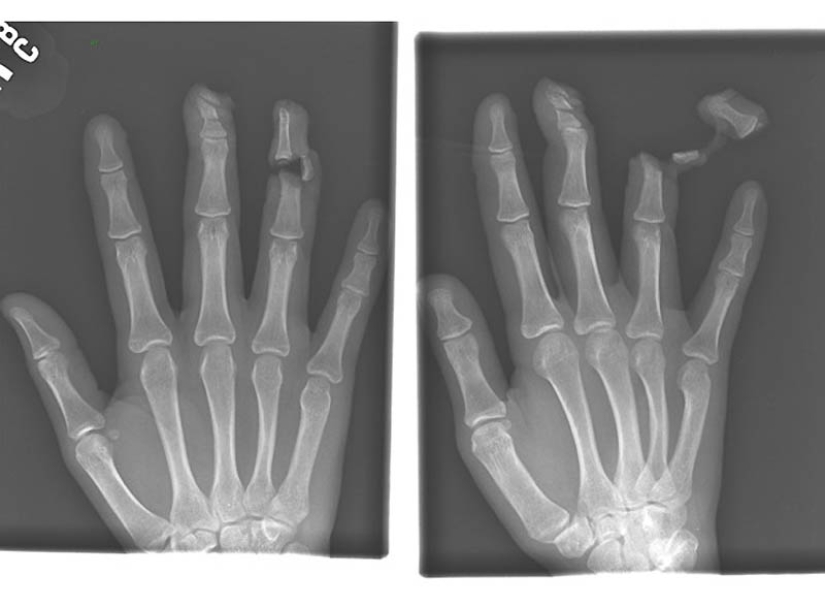

4. A nail in the bones of the index and middle fingers of an adult male.